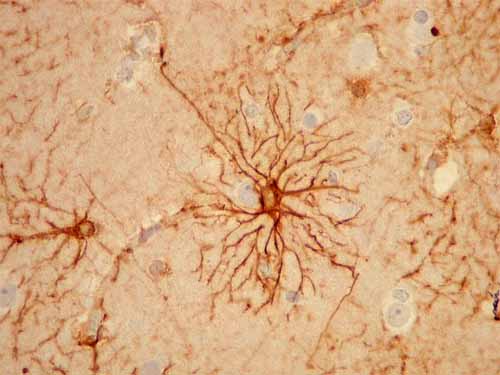

Astrócitos – Existem dois tipos destas células:

. Protoplasmáticos: com várias ramificações curtas, essencialmente na matéria cinzenta;

Fig-4 – astrócito protoplasmático

. Fibroso: com prolongamentos longos com poucas ramificações, essencialmente na substancia branca.

Fig-5 – astrócito fibroso

Funções: -captam os neurotransmissores - funções metabólicas - constituintes do esqueleto do tecido nervoso - síntese de factores Neurotróficos. - têm prolongamentos inseridos nos vasos sanguíneos